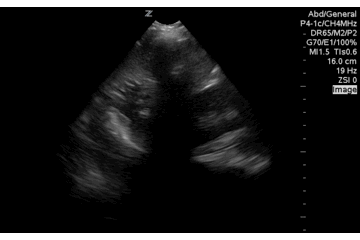

Another example fanning posterior and anterior. A better demonstration of rugae, contained fluid within the stomach and a negative LUQ FAST view.